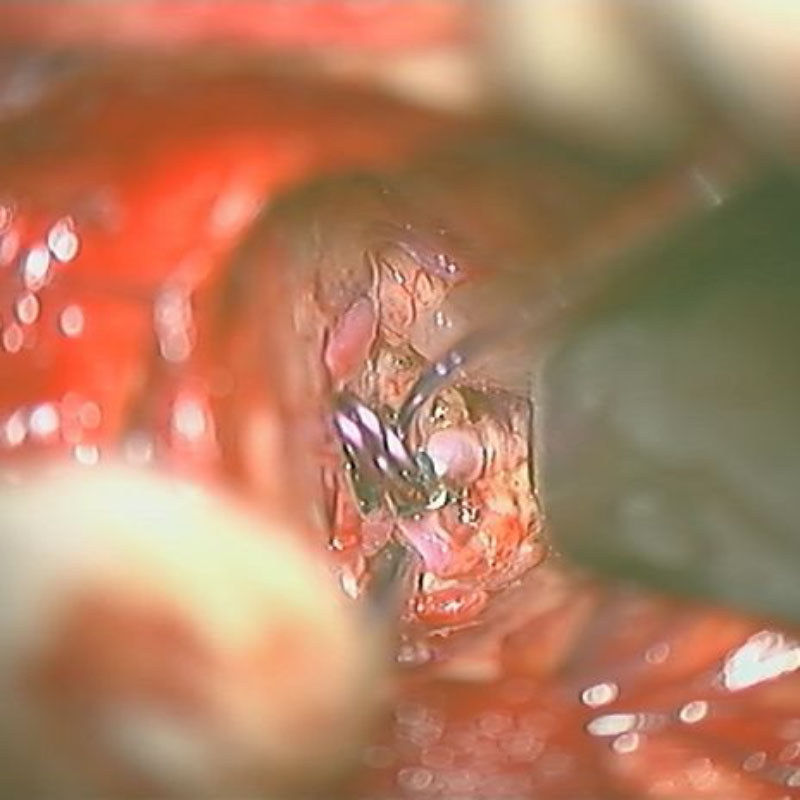

※ 画像をクリックすると拡大表示します。症例No.をクリックすると詳細ページを表示します。

クリップ前

クリップ後

手術後